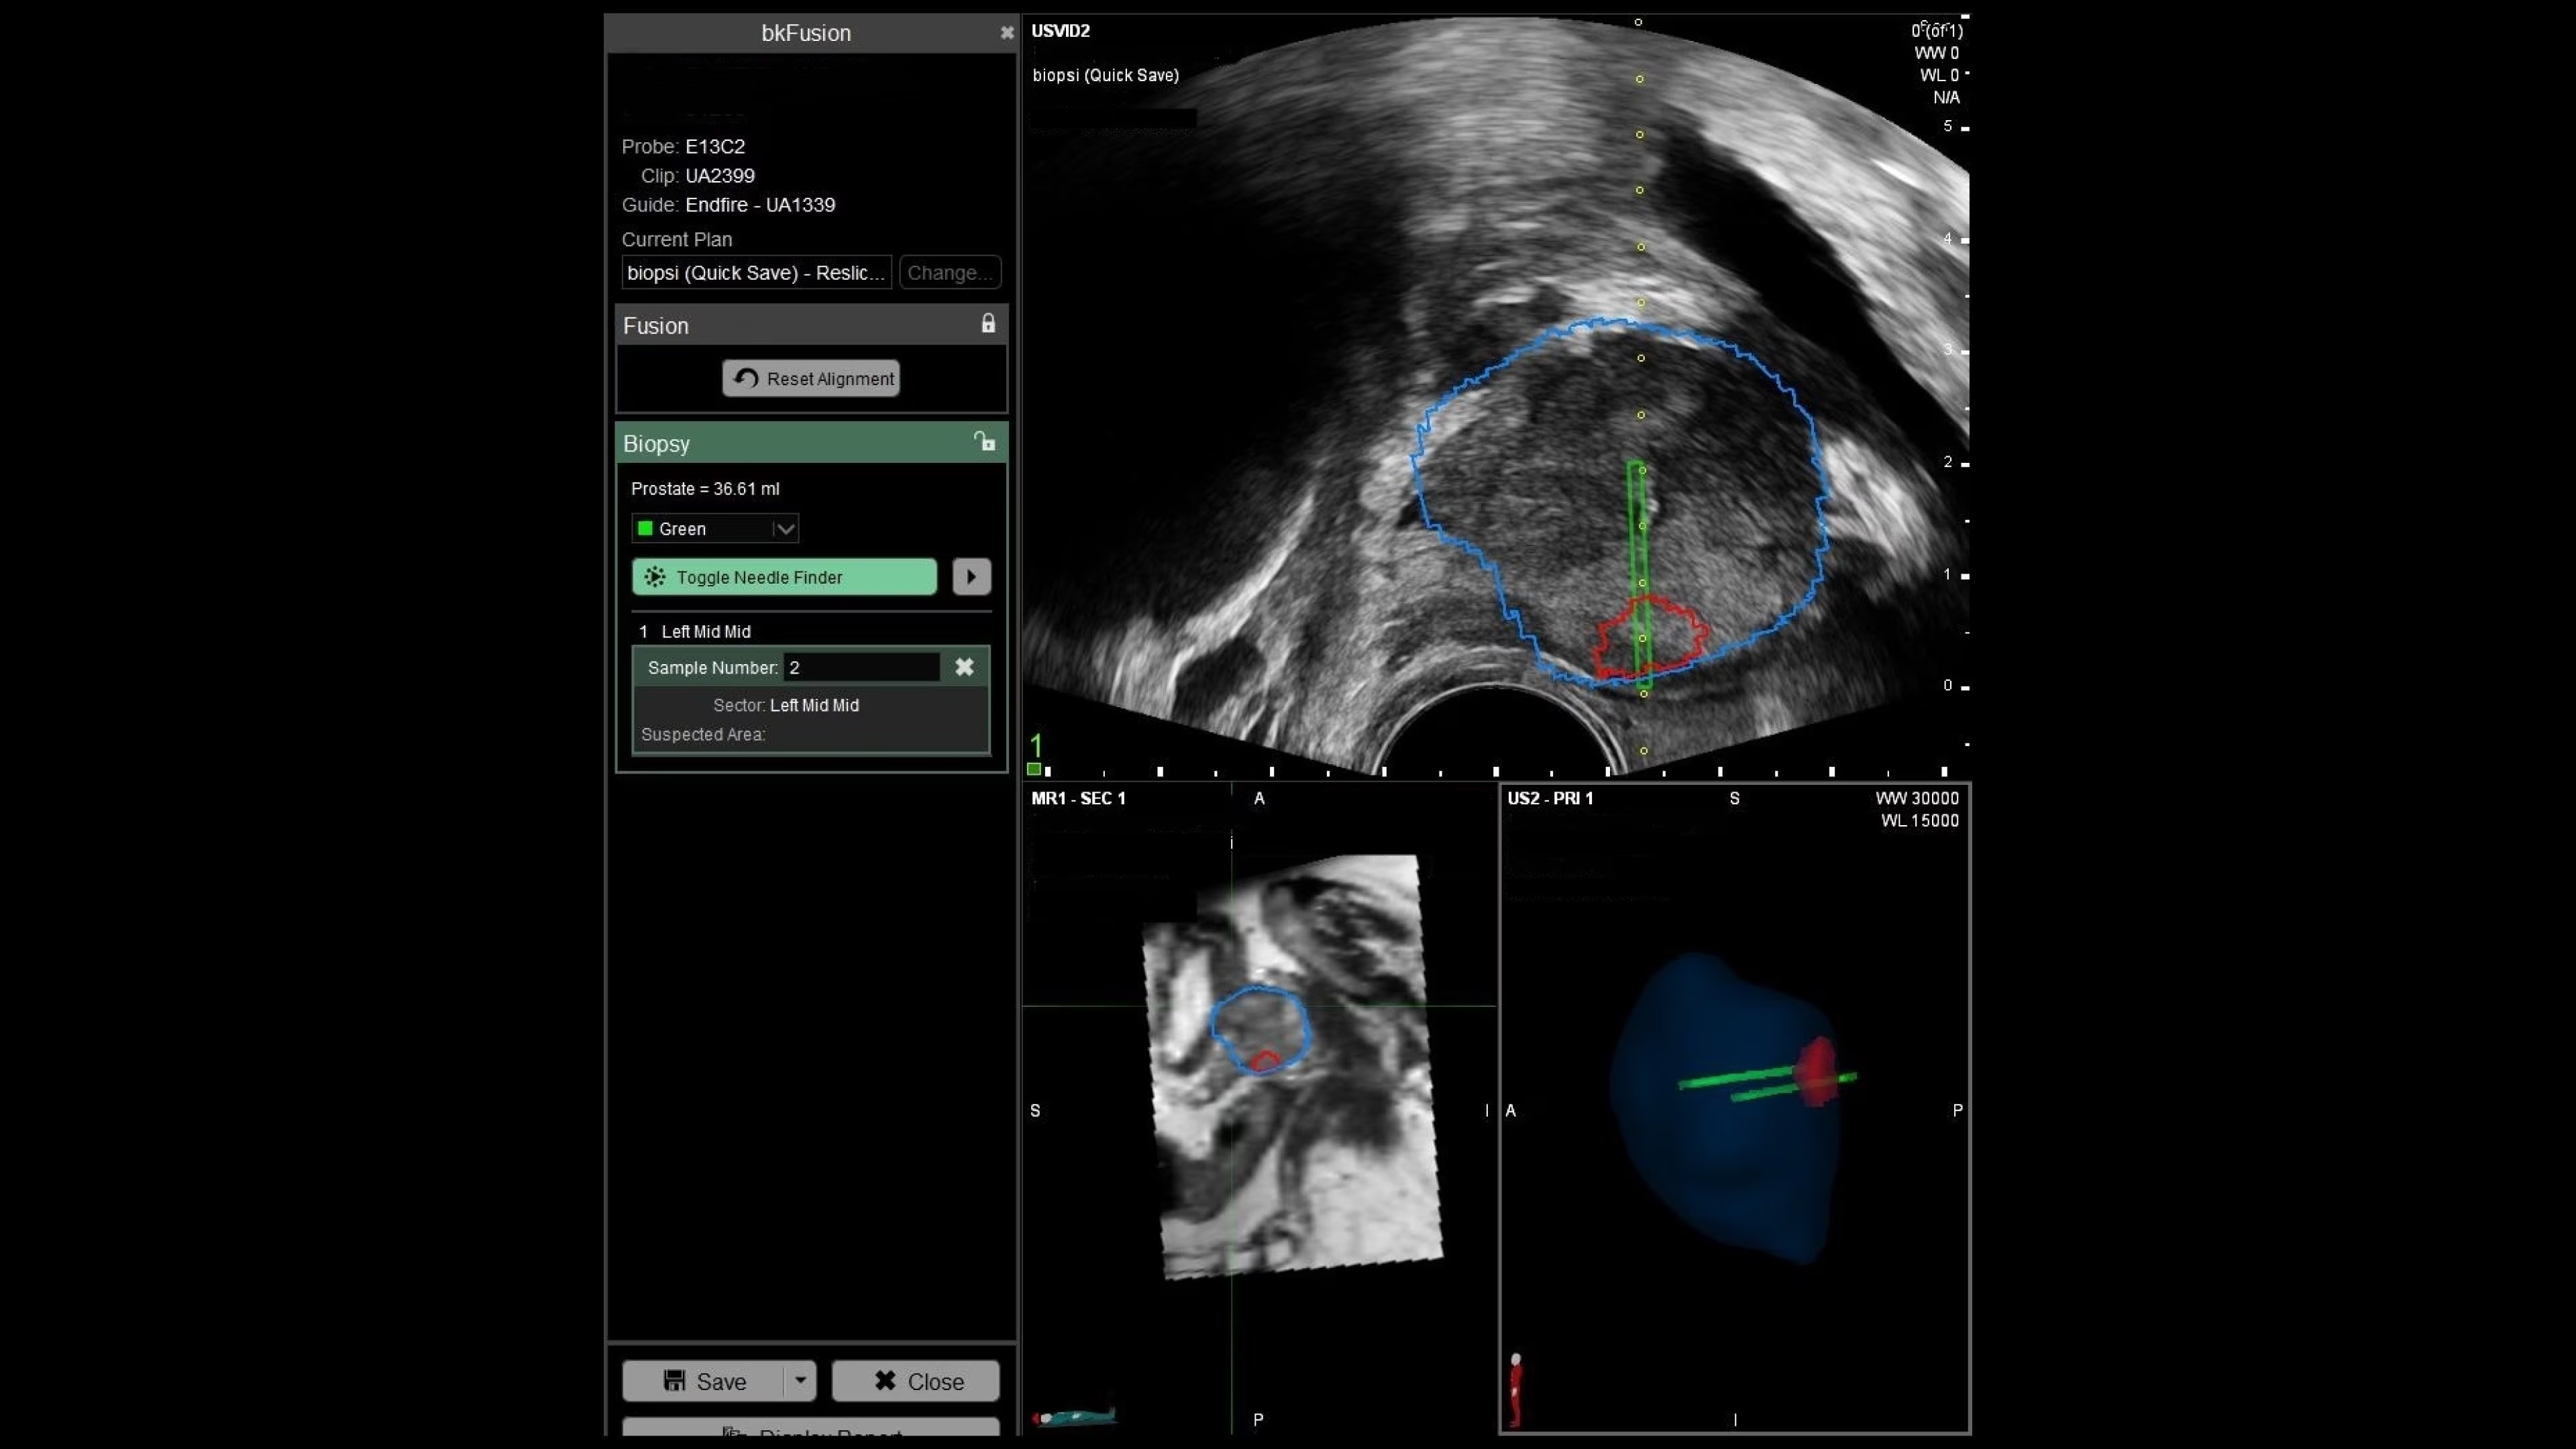

With bkFusion, confidently target your biopsy with clear visualization of organ borders to detect registration errors or deformations in real-time. bkFusion, MRI-ultrasound fusion biopsy solution features proprietary imaging algorithms developed with high spatial, temporal, and contrast resolution for advanced visualization.

bkFusion has proven to accurately detect 84% of PIRADS 3-5 lesions and up to 81% GG>=2 cancer.¹

Enhance biopsy accuracy with Predictive Fusion®

Predictive Fusion® is the proprietary registration method allowing you to imediately see any errors in the overly of MRI and ultrasound images before and during the procedure. Utilizing rigid 2D slice registration, it eliminates distortion in merging 3D shapes, ensuring precise MRI-ultrasound fusion. If changes are needed, make simple, one-touch, micro-adjustments to updte the registration without calibration steps or 3D sweeps. Enhance your prostate biopsy accuracy with this advanced technology.